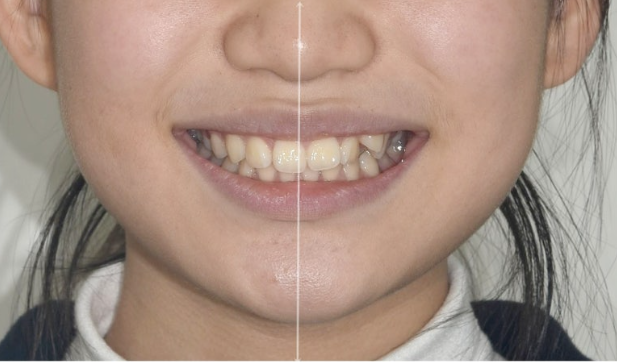

이제 전 후 비교 보겠습니다.

23.02~25.05

코와 인중이 맞아진 상악 중심선

2mm의 어긋남이 해소가 되어 맞아진 상악과 하악 치아중심선

적절한 입동굴로 아담해진 치열

완만한 U자형의 스마일라인

미소가 훨씬 정돈되고 깔끔한 느낌이 듭니다.